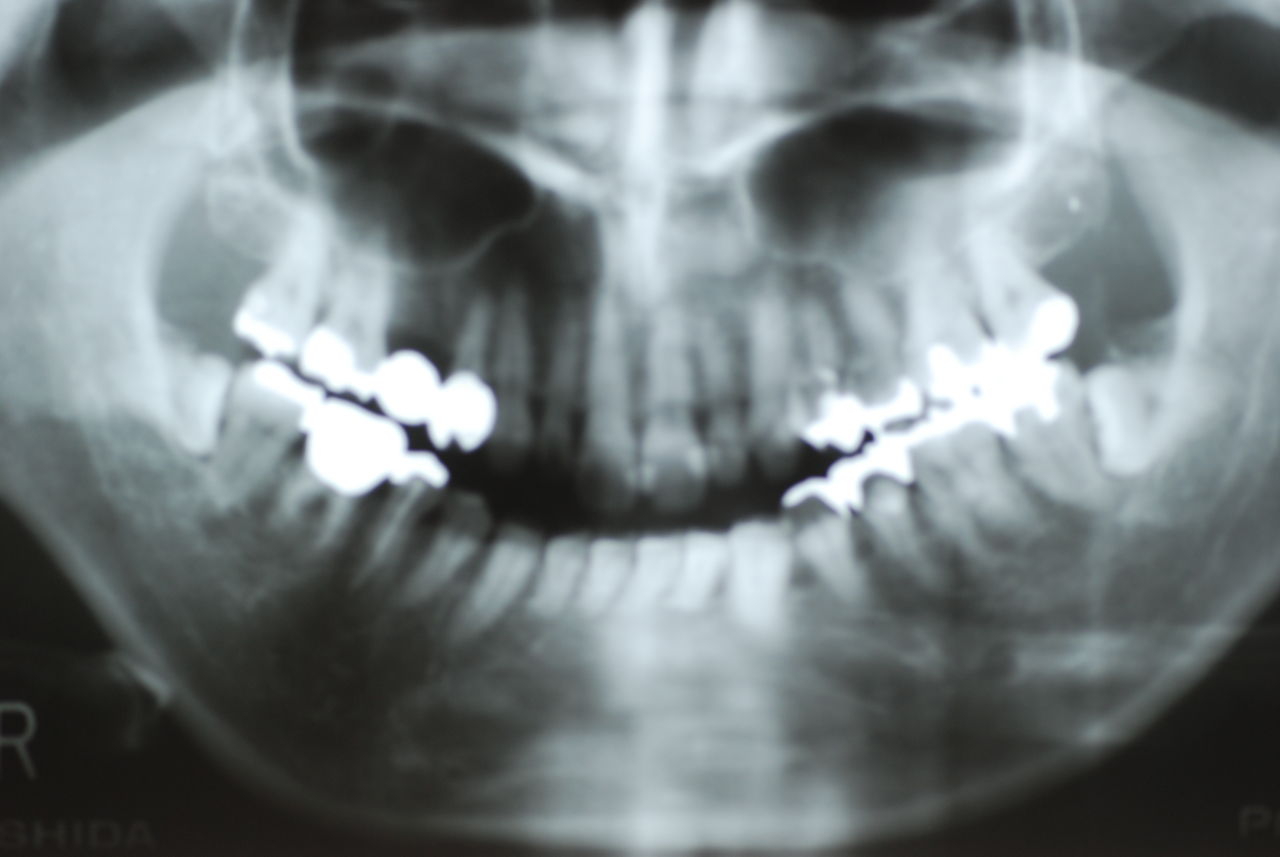

下記はかなりうまくいった方です。

平成9年治療、虫歯と神経の処置、歯周病の治療

2012,7月来院

欠けたところを埋めておしまいです。